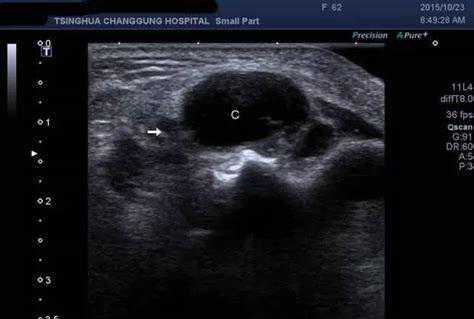

2、超声检查

超声刚好能够弥补X线成像对浅表组织的不足,而且对像腱鞘囊肿这种浅表性软组织肿物敏感性较高,说白了就是看我们身体浅表的肌肉、软组织、肿物比较好。

目前也成为门诊中用来检查患者是否为腱鞘囊肿的主要检查。

超声检查图像下,大多数腱鞘囊肿边界清晰、囊肿壁厚、内部回声增强。而有一些实性外观的腱鞘囊肿虽然不常见,但可能酷似良性肿瘤,需要进一步行进一步检查完善。

看看这个超声检查,是不是可以看到一个圆圆的东西,很清楚?